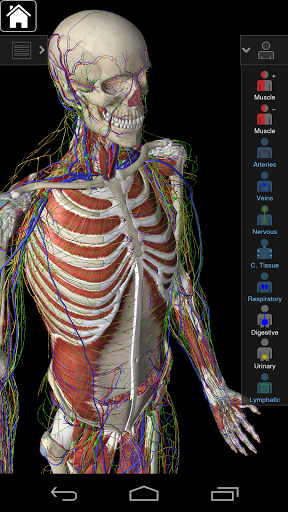

Cette application comprend l'anatomie essentielle pour 10 systèmes:

⁃Squelettique

⁃Muscles

⁃Tissu conjonctif

⁃Veines

⁃Artères

⁃Nerfs

⁃Respiratoire

⁃Digestif

⁃Urinaire

⁃Lymphatique

⁃ comprend également le cerveau et le cœur

La fonctionnalité intelligente trouvée dans l'application permet à l'utilisateur de dépouiller les couches de muscle via l'outil «scalpel». Cette application offre aux utilisateurs la possibilité d'activer / désactiver des systèmes sans avoir à désélectionner des structures individuelles ou à se frayer un chemin à travers une multitude d'onglets régionaux prédéfinis, comme d'autres applications.

Essential Anatomy 3 est conçu en pensant à l'utilisateur - le corps lui-même devient l'interface. Contrairement à d'autres applications 3D, qui reposent sur des arrangements anatomiques prédéfinis et des dissections régionales pour guider l'utilisateur, l'Anatomie 3 essentielle de 3D4Medical vous permet de trouver ce que vous recherchez sans complication.